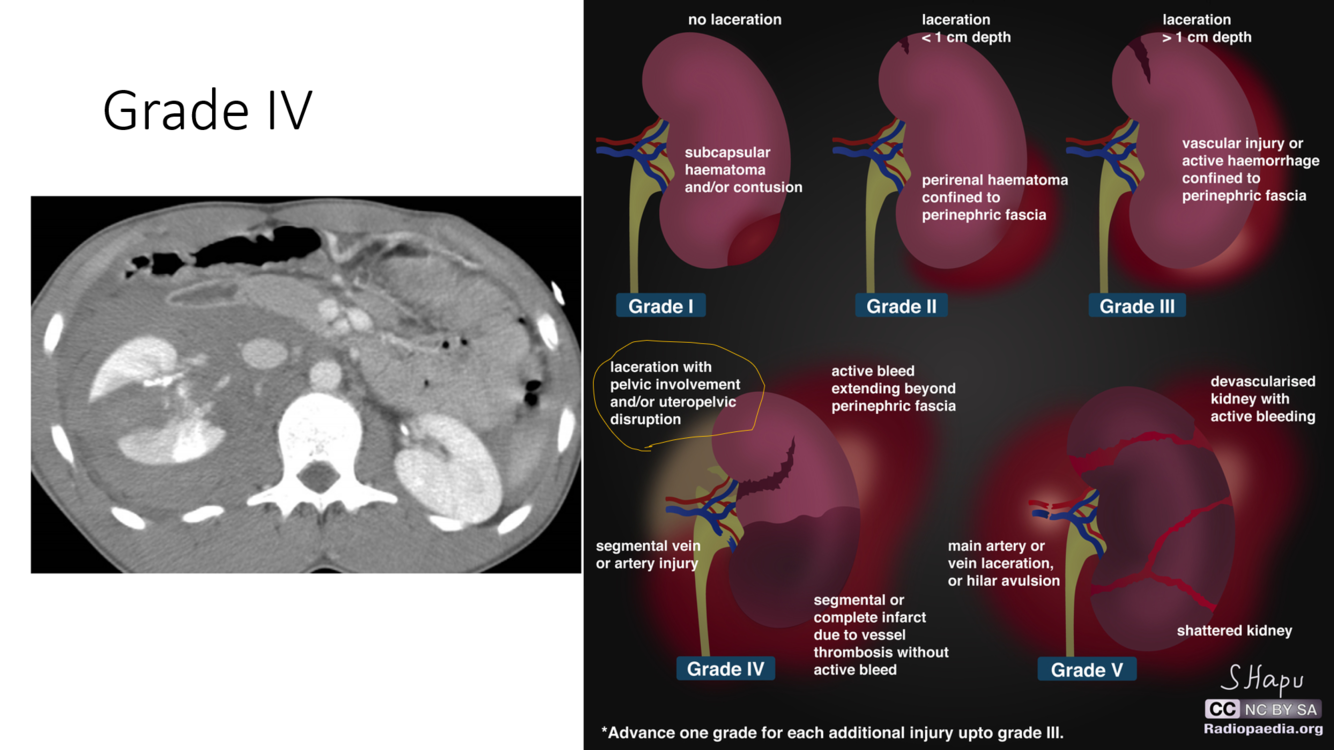

trauma grade

IV

Next step?

Take it out!!